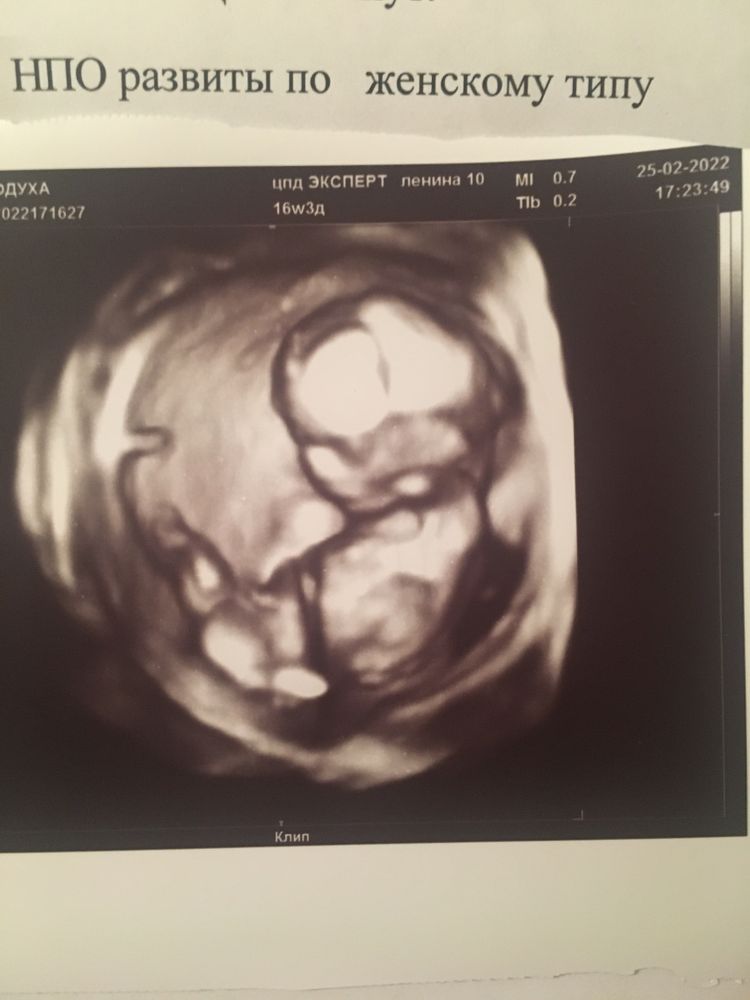

Пол ребёнка в 16 недель

Дочку в 16 недель определили, не ошиблись. С сыном пока не знаю😁 Но в 16 недель, да в 3д уже точно всё должно быть. Хотя вероятность ошибки есть всегда, главное чтобы здоровый малыш был, а не пол)

В 15 недель точно сказали и показали парня)) на таком сроке ошибки мало вероятны, но все же бывают, а у вас тут 3д, поэтому думаю, все верно вам определили. Поздравлю с принцесской 🧚🏼